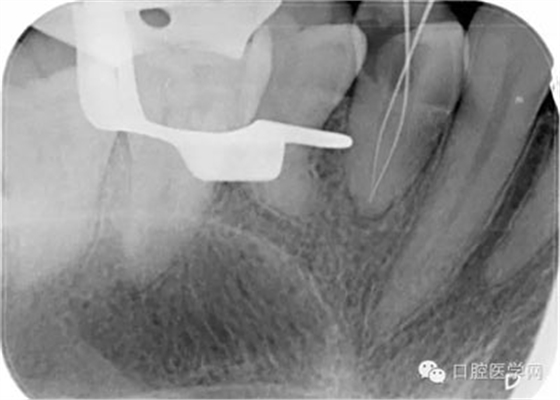

第五步:確定根管長度,臨床上常用方法為根測(cè)+X片+吸潮紙尖法。

根測(cè)法:用不銹鋼K銼插入根管直至有阻力部位,夾入根管測(cè)量儀器測(cè)量,一般距離根尖顯示0.5MM為工作長度。

X片法:X線片上可以清楚看到根管銼插入根管的深度,但因看到的是解剖性根尖,而根尖孔大多數(shù)開口于側(cè)方,所以X線片 到達(dá)根尖時(shí),實(shí)際是超出了。數(shù)據(jù)顯示根尖孔距離根尖可以從0.5mm-3mm之間。

(我的助手是拍個(gè)X片就像是段譽(yù)練的六脈神劍,時(shí)靈時(shí)不靈。不過這張片,我還是覺得美呆了。)